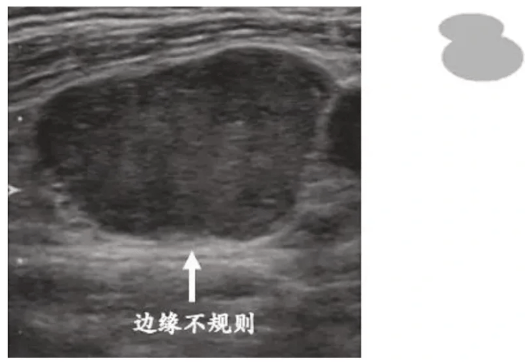

⑤边缘不规则

淋巴结纵横比≥1,边缘模糊,成角或毛刺状,提示肿瘤突破淋巴结被膜侵犯周围组织。